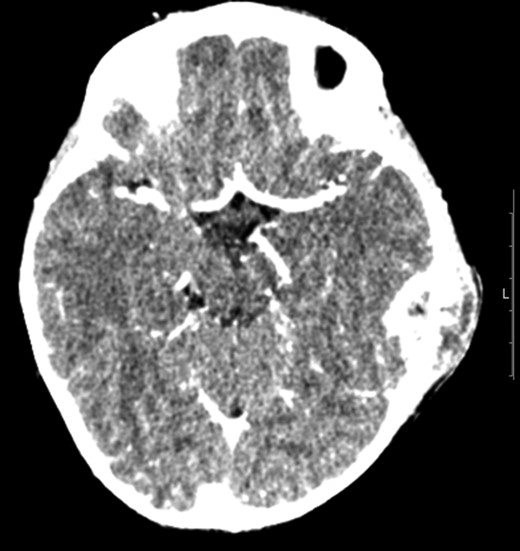

A CT scan of the patient at this point showed mastoiditis, a subperiosteal abscess and extradural abscess with extensive bony defects (Figs 1 and 2). The patient was initially started on IV ceftriaxone and metronidazole. Upon discussion with ENT specialists he underwent a left sided mastoid exploration and drainage of the extradural and peri sigmoid sinus collection on Day 2 of his admission. Surgical exploration found a large parietal subperiosteal abscess with bony defects and granulation tissue connecting with an extradural abscess. Histological diagnosis showed evidence of granulomatous osteomyelitis due to necrotizing granulomatous inflammation. Initial Zeihl-Neelson and Wade Fire stains for acid fast bacilli in tissue culture were negative.

Transverse computer tomography with contrast (angiography), showing the extent of the extradural abscess (black asterisk). L = Left; R = Right. It shows that the left extracranial soft tissue abscess communicates freely through the parietal skull vault defect with the large intracranial extradural abscess, which spans the left tentorial leaflet.